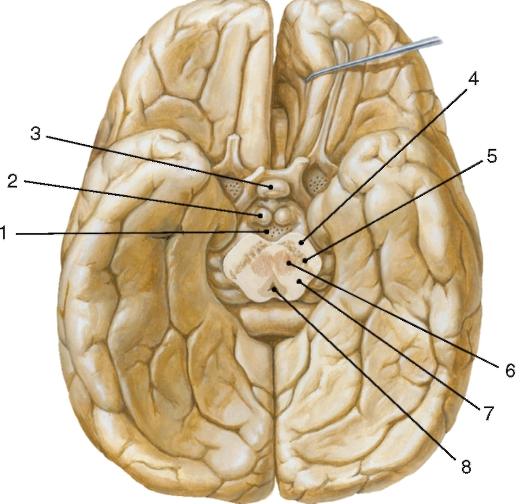

Необычные объекты: Переднее продырявленное вещество

Раздел: Альбом открытий